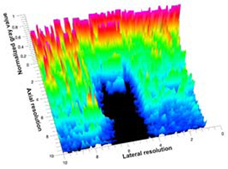

3.3. B-Mode Images

3.5. Echogenicity

4.1. Ultrasonography and Aerogel Dimensional Analyis

| Aerogel Type | US Image | Normalized Intensity Map | 3D Intensity Map | |

|---|---|---|---|---|

| 1 | Muscle |  |  |  |

| 2 | X-silica |  |  |  |

| 3 | X-silica-La2O2S:Eu |  |  |  |

| 4 | SMPU-Mix-14 |  |  |  |

| 5 | SMPU-Mix-18 |  |  |  |

| 6 | BRF-CA |  |  |  |

| 7 | ARF-CA |  |  |  |

| 8 | X-Ca-Alg-2 |  |  |  |

| 9 | X-Ca-Alg-1 |  |  |  |